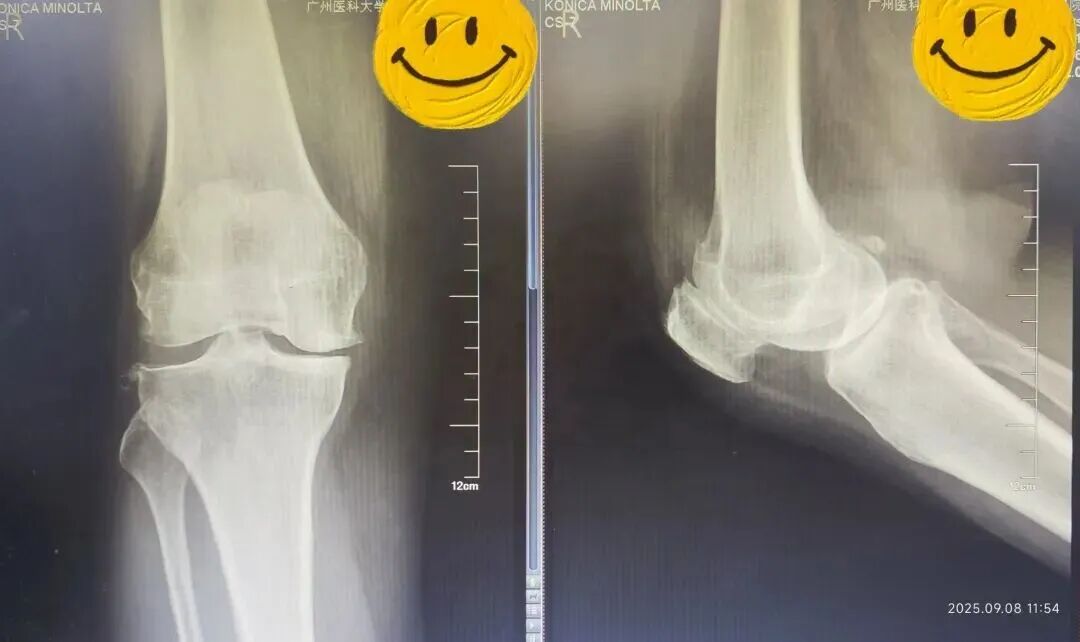

术前(左)术后(右)X线光片对比

接诊的骨科主任陈东峰发现,温女士左膝关节轻度肿胀,关节活动受限,有疼痛症状,结合影像学表现,符合膝关节退行性骨关节病的典型特征,建议她入院治疗。

对于不同程度的骨关节病,医生会提供保守治疗(药物和物理治疗)、截骨术和全膝关节置换术等治疗办法。考虑到温女士的病变主要集中在前内侧区域,症状局限在膝关节内侧,没有明显的内外翻畸形,最终选择了部分膝关节置换术。

在麻醉科配合下,陈东峰手术团队清除了增生的滑膜组织,去除了骨赘,对关节进行了适当松解,术中发现关节面磨损严重,软骨下骨暴露,内侧半月板后角脱位。医生精心安置了人工关节假体,替代了已经损坏的关节面。